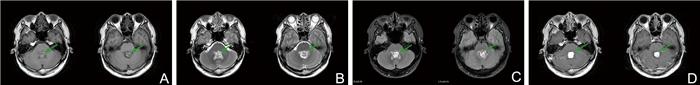

Analysis of the diagnostic efficacy of digital breast tomosynthesis in patients with early-stage breast cancer

YANG Yan, ZHAO Yunian, MAO Changfei, TANG Xiaowen, LI Dongxue

2025, 23(6): 1004-1007. doi: 10.16766/j.cnki.issn.1674-4152.004053

67 3

Abstract:

Objective  To investigate the diagnostic efficacy of digital breast tomosynthesis (DBT) in detecting early-stage breast cancer and compare its efficacy with that of magnetic resonance imaging (MRI).  Methods  A retrospective analysis was conducted on 50 patients diagnosed with early-stage breast cancer between January 2023 and December 2023. All patients underwent imaging examination, with complete and high-quality imaging data prior to pathological examination. The pathological findings were used as the gold standard to compare detection accuracy, sensitivity, and specificity DBT and MRI, as well as breast cancer staging consistency between imaging and pathology.  Results  The rates of missed diagnoses, misdiagnosis, and accuracy in detecting breast lesions for DBT were 4.00% (2/50), 6.00% (3/50), and 90.00% (45/50), respectively. Compared with MRI [2.00% (1/50), 4.00% (2/50), and 94.00% (47/50)], these differences were not statistically significant. Based on the pathological examination results as the gold standard, there was no statistically significant difference in the diagnostic results of DBT for breast cancer type classification. A total of 87 breast masses (54 malignant and 33 benign) were identified in 50 patients with early-stage breast cancer. DBT demonstrated lower diagnostic sensitivity and negative predictive value than MRI, it exhibited higher specificity and positive predictive value. Overall diagnostic accuracy was comparable between the two modalities. The cost-benefit ratio (CER) for DBT and MRI were 3.25 and 12.17, respectively, and the incremental cost-benefit ratio (ICER) for MRI relative to DBT was 713.91.  Conclusion  Digital breast tomosynthesis offers high accuracy and favorable cost-effectiveness in the diagnosis of patients with breast cancer, making it a valuable tool worthy of broader clinical application.